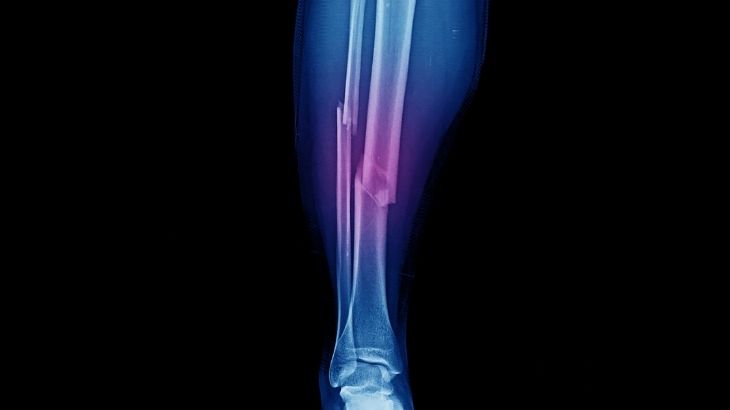

Fasyotomi, kas gruplarını saran fasya adı verilen bağ dokusunun cerrahi olarak kesilmesi işlemidir. Bu müdahale, genellikle kompartman sendromu gibi acil durumlarda uygulanır. Kompartman sendromunda, kan dolaşımının sağlıklı şekilde devam edebilmesi için fasya açılarak kasların rahatlaması amaçlanır. Müdahale edilmediğinde dokuların beslenmesi bozulabilir ve kalıcı sinir ile kas hasarları gelişebilir. Fasyotomi, zamanla yarışılan ve kararın gecikmesinin uzuv kaybına yol açabileceği bir cerrahi işlemdir. Hastanın durumuna göre tek bir kesiyle sınırlı kalabileceği gibi birden fazla bölgeyi kapsayacak şekilde de planlanabilir.

Fasyotomi, kas grupları içinde tehlikeli düzeye ulaşan basıncı azaltmak için yapılan cerrahi müdahaledir. Müdahale sırasında kasları saran fasya dokusu kesilerek dokuların rahatlaması sağlanır. Bu sayede sinirler, damarlar ve kaslar üzerindeki baskı ortadan kaldırılır.

Akut kompartman sendromu, genellikle travma sonrası hızla gelişen ve acil müdahale gerektiren klinik bir tablodur. Kas dokusu içinde biriken basınç, sinirleri ve damarları kısa sürede sıkıştırarak geri dönüşü olmayan hasarlara yol açabilir. Bu durum birkaç saat içinde tedavi edilmezse uzuv kaybına kadar gidebilecek sonuçlar ortaya çıkabilir.

Basınç artışı, kas dokusu içinde oluşan kanamalar, ödem ya da sıvı birikimi sonucunda hızla kritik düzeye ulaşabilir. Bu durum, özellikle travma sonrası geliştiğinde sinir ve damar fonksiyonlarını tehdit eder. Süreç doğru yönetilmezse, kas içi basınç kontrolsüz biçimde yükselerek doku kaybına zemin hazırlayabilir.

Fasyotomi ameliyatı, cilt ve derin dokular üzerinden yapılan kesilerle kasların üzerindeki fasya tabakasının açılmasını içerir. Bu işlem sayesinde içerideki basınç düşürülür ve kaslarla sinirlerin yeniden kanlanması sağlanır. Gerekirse açık bırakılan alanlar ilerleyen günlerde tekrar değerlendirilerek ikinci bir girişim yapılabilir.